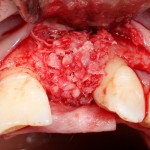

В этом случае остеопластика делается отдельной процедурой. Ее принципы точно те же, но уже без импланта. Например:

Имплантировать в таких условиях — заведомо обрекать себя на хреновый, с точки зрения эстетики и функциональности, результат. Поэтому первым этапом проводим остеопластику. Объем небольшой, использовать в таких объемах костный блок не очень рационально. Воспользуемся аутокостной стружкой и мембраной.

Сначала фиксируется BioGide. Это легко:

Затем укладывается и конфигурируется аутокостная стружка: